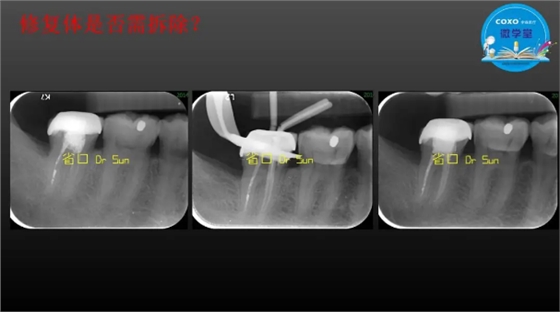

主任医师,牙体牙髓副主任, 广东省口腔医院牙体牙髓科 主任医师。2003年硕士研究生毕业,研究方向为牙体牙髓病学,擅长于牙体牙髓病的诊断、龋齿、牙髓炎、根尖周病的治疗以及前牙美容修复。